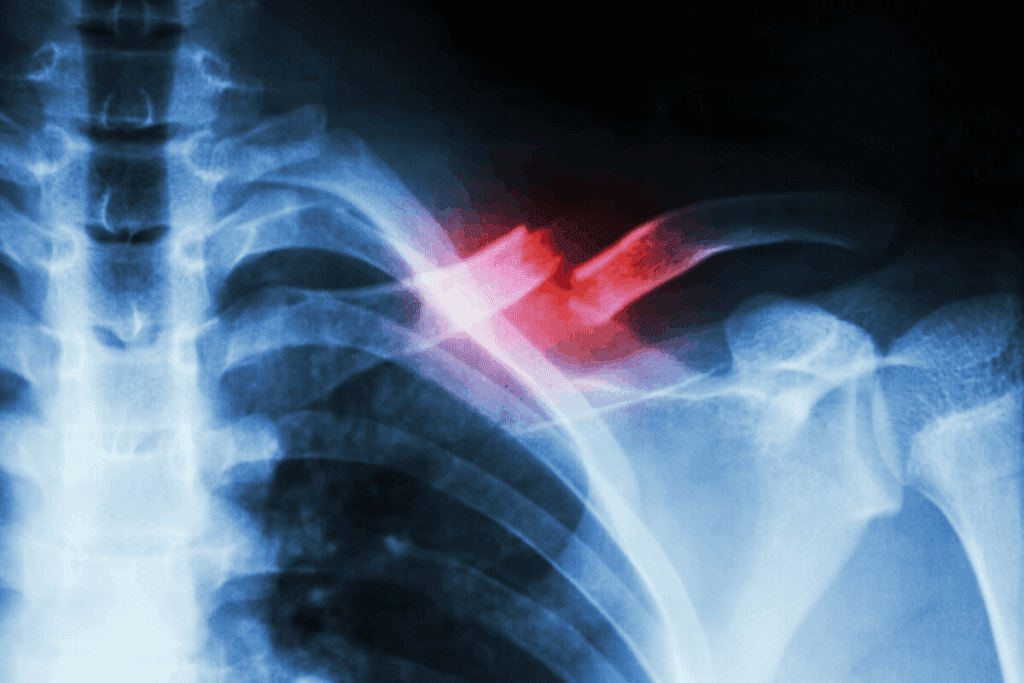

Shoulder Arthroscopy: The Third Most Common Orthopedic Surgery

Orthopedic statistics show that shoulder arthroscopy is the third most common surgery. This highlights its key role in orthopedic care.

Statistical Evidence Confirming Its Third-Place Ranking

Studies and data confirm that shoulder arthroscopy is among the top three surgeries. A review of orthopedic surgery statistics shows an increase in shoulder arthroscopy over the last decade.

The number of shoulder arthroscopy procedures has grown. This is true for the younger, active population. It’s due to more awareness of shoulder injuries and better arthroscopic techniques.

Shoulder arthroscopy is a key surgery in orthopedics. It helps doctors see inside the shoulder joint. This is very useful for treating many shoulder problems.